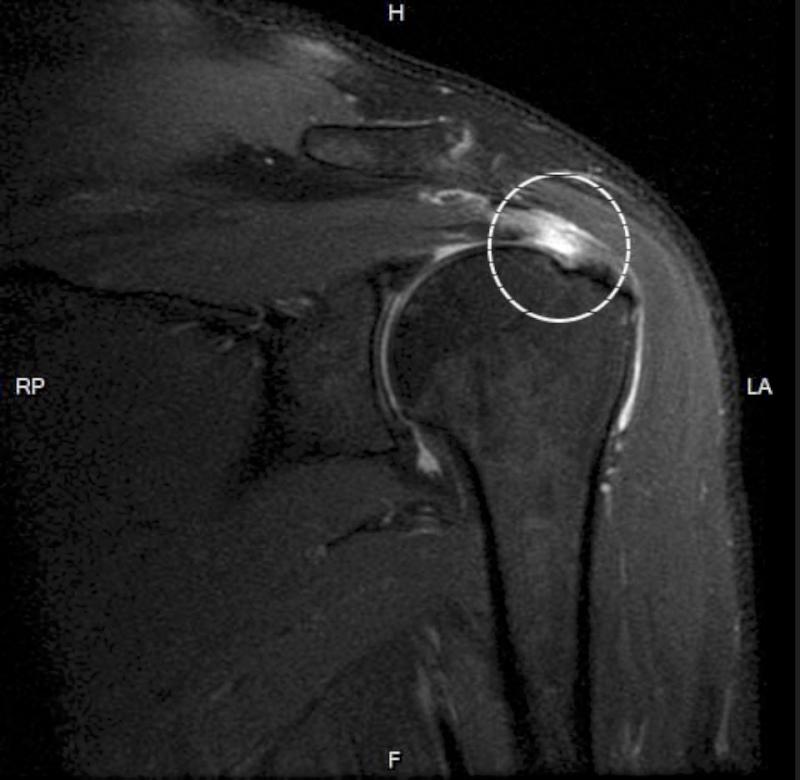

高市60歲製麵廠負責人揉麵團及搬重物,長期導致肩膀、手指疼痛無力,就醫經核磁共振檢查發現肩膀旋轉肌袖斷裂,進一步確診罹患板機指,5年間6隻手指症狀陸續顯現,接受旋轉肌袖修補及肩峰成形手術搭配復健治療,症狀獲得緩解,手臂能輕鬆抬起,高雄中正脊椎骨科醫院骨科醫師劉梅玲說,廚師、美髮師、家管等罹患板機指風險相對較高,建議適度休息。

劉梅玲說,民眾如手指疼痛、感覺卡卡,可先熱敷並適度伸展,症狀未見改善,應求助專業醫師檢查治療。圖/中正脊椎骨科醫院提供、文/高培德